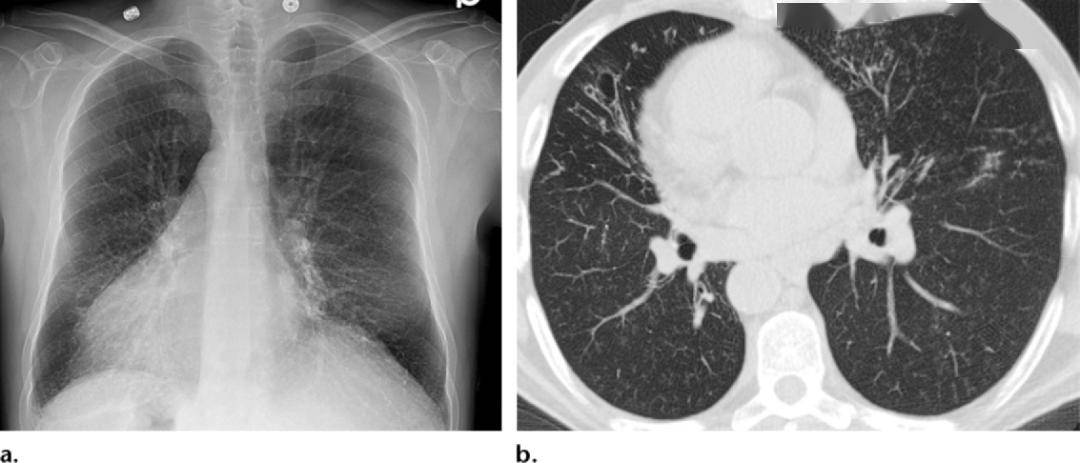

图4-42 支气管扩张x线表现a.胸部正位像;b.侧位像.